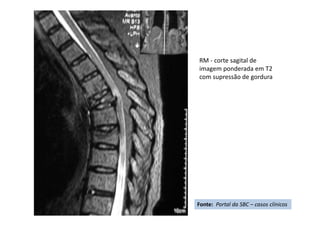

RM - corte sagital de

imagem ponderada em T2

com supressão de gordura

imagem ponderada em

T2

Fonte: Portal da SBC – casos clínicos